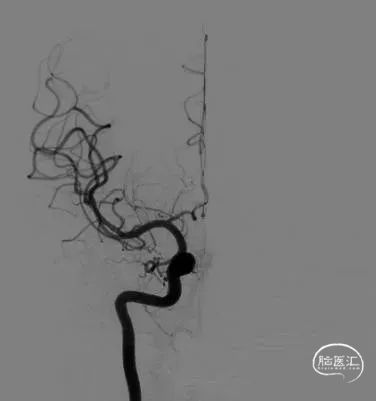

分叶状前交通宽颈动脉瘤

动脉瘤呈分叶状,瘤顶及瘤颈处见3个子囊。

手术策略:支架辅助弹簧圈栓塞

术前影像

微导丝引导下,将微导管送入右侧大脑前动脉A1段,反复调整进入前交通动脉瘤内向下的分叶中,填入成篮圈后,依次置入若干枚Jasper®弹簧圈。支架半释放覆盖瘤颈,调整弹簧圈,稳定后解脱。